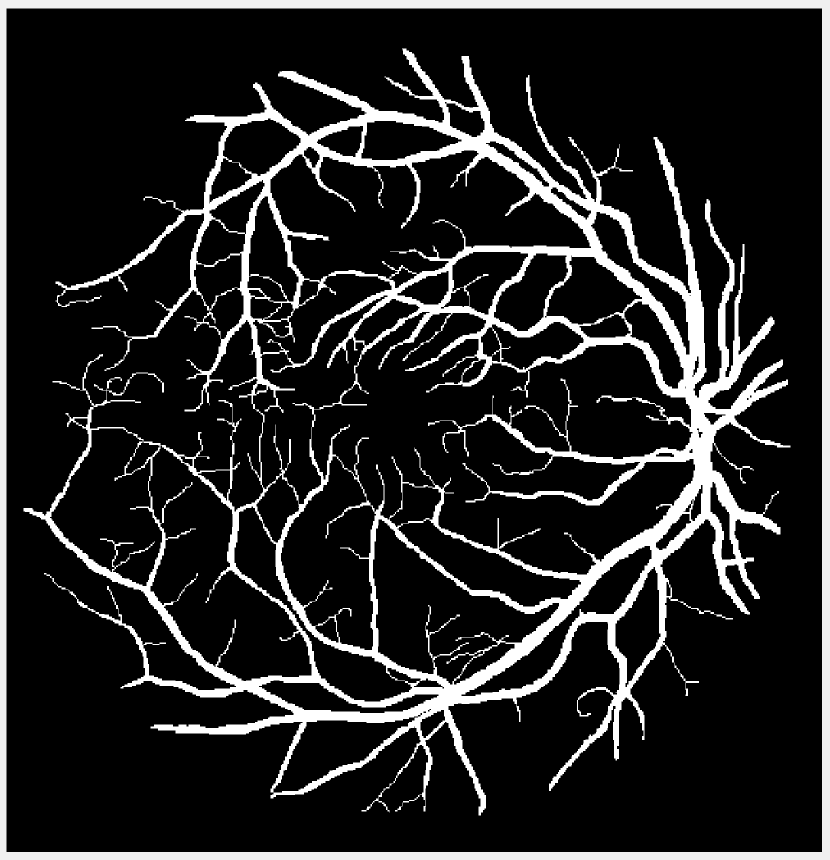

Refer to caption

(b) Vessel 2

Figure 1: Original images for testing. (a)-(c) Retinal vessel images from the DRIVE dataset [23]. Image size is 584×565584565584\times 565 with pixel intensities 191 (vessel) and 104 (background). (d)-(g) Brain images from the BrainWeb dataset [24]. Image size is 104×8710487104\times 87 with pixel intensities 10 (background), 48 (cerebrospinal fluid), 106 (grey matter), and 154 (white matter).

We compare the performance of the proposed TTV-regularized image segmentation model with its counterparts regularized by (isotropic) TV [8], TVp [12], and AITV [15]. The algorithm we use for TV is similar to Algorithm 1 in that we use the 2,1subscript21\ell_{2,1} proximal operator in (7). For TVp, we use the ADMM algorithm following [12] but without the bias term for fair comparison and set p=1/3𝑝13p=1/3 as suggested. For AITV, we use the difference-of-convex algorithm (DCA) [25] designed in [15] and set α=0.5𝛼0.5\alpha=0.5 as suggested. The image segmentation models are applied to the images shown in Figure 1. For Figures 1(a)-1(c), we perform binary segmentation to identify the retina vessels, while for Figures 1(d)-1(g), we perform multiphase segmentation (N=4𝑁4N=4) to identify the cerebrospinal fluid (CSF), grey matter (GM), and white matter (WM) separate from the background. We evaluate the segmentation performance by two metrics: DICE index [26] and Jaccard similarity index [27]. The parameters for each segmentation method are carefully tuned so that we obtain the best DICE indices. Specifically, for Algorithm 1 that solves (4), we set β1=β2=0.25subscript𝛽1subscript𝛽20.25\beta_{1}=\beta_{2}=0.25 and find the optimal parameter λ𝜆\lambda in the range [0.0025,0.05]0.00250.05[0.0025,0.05] for both binary and multiphase segmentation. For binary segmentation, we select the best value for a{5,10,100}𝑎510100a\in\{5,10,100\} while for multiphase segmentation, we select for a{1,5,10}𝑎1510a\in\{1,5,10\}. Algorithm 1 is initialized with the results of fuzzy c𝑐c-means clustering [28] and it terminates either when UtUt1FUtF<104subscriptnormsuperscript𝑈𝑡superscript𝑈𝑡1𝐹subscriptnormsuperscript𝑈𝑡𝐹superscript104\frac{\|U^{t}-U^{t-1}\|_{F}}{\|U^{t}\|_{F}}<10^{-4} or after 200 iterations. The experiments are performed in MATLAB R2022b on a Dell laptop with a 1.80 GHz Intel Core i7-8565U processor and 16.0 GB of RAM. The code for Algorithm 1 is available at https://github.com/JimTheBarbarian/Official-TTV-Segmentation.

(a) Vessel 1

Figure 2: Segmentation results of Figures 1(a)-1(b) (after normalization) corrupted by Gaussian noise of mean 0 and variance 0.01.

Before applying the segmentation algorithms, the images in Figure 1 are normalized to [0,1]01[0,1] followed by Gaussian noise corruption. The retina vessel images are corrupted with Gaussian noise of mean 0 and variance 0.01. Table I reports the performances and times of the segmentation methods on the retina vessel images while Figure 2 shows some of their results. TTV (a=10,100)𝑎10100(a=10,100) has the highest DICE and Jaccard similarity indices across the three images although requiring about 80 seconds to complete, thereby being slower than TV and TVp. The brain images are corrupted with Gaussian noise of mean 0 and variance 0.04. Table II reports the performances and times of the multiphase segmentation, while Figure 3 shows the segmentation results of Figure 1(g). By its DICE and Jaccard similarity indices, TTV (a=1)𝑎1(a=1) is best at segmenting CSF across the four images while TTV (a=5,10)𝑎510(a=5,10) remains competitive against AITV in segmenting GM and WM. On average, TTV (a=1,5)𝑎15(a=1,5) is among the top two best-performing methods. Although it can be outperformed by AITV, it is at least three times faster. In Figure 3, we see that TTV (a=5)𝑎5(a=5) is most effective in segmenting CSF, especially compared to TV and TVp. Moreover, comparable to TV and AITV, it is able to identify most of the GM and WM regions. Overall, using TTV, the proposed method is able to effectively identify narrow, thin regions such as the retina vessels and CSF.